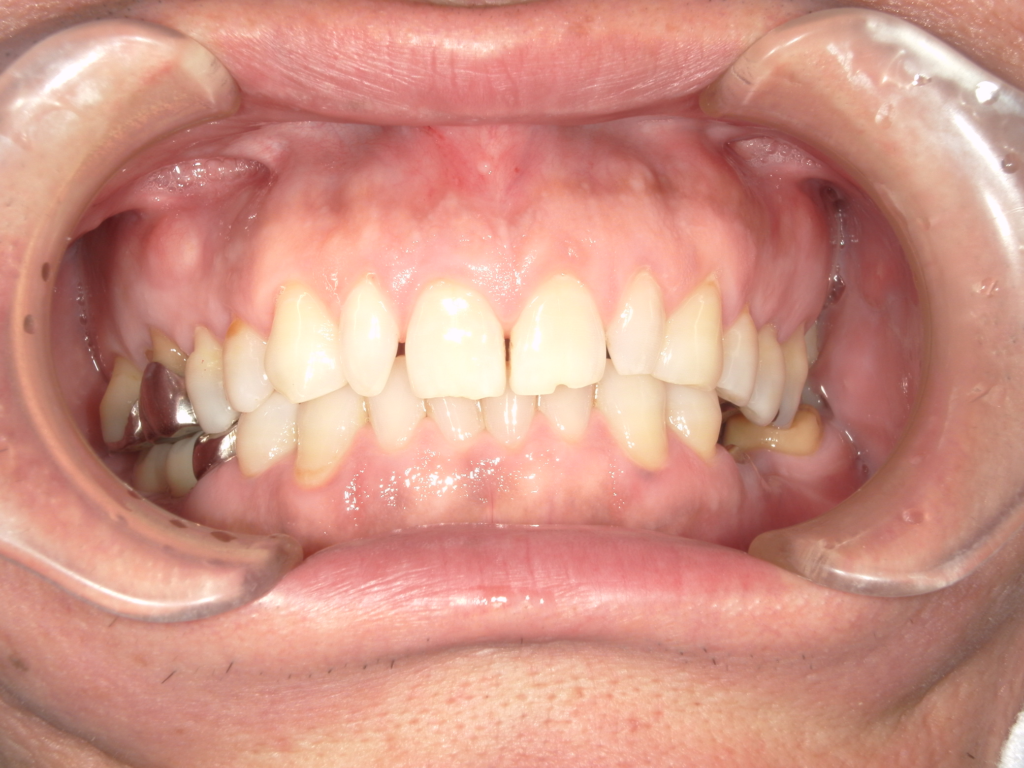

Y様インプラント実例 #44

左の上下の奥歯をインプラントで治療しています。

左下の奥歯は歯を抜くのと同時にインプラントの埋め込みを行っています。

被せものは上下、セラミックスで作っています。

治療前

治療後